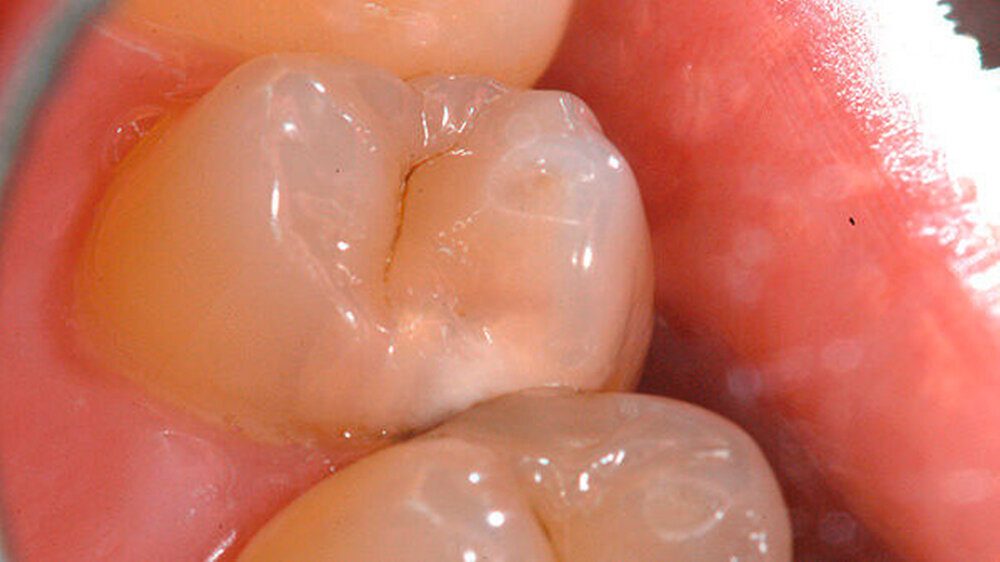

-Schnee positiv und in der Perkussionsprobe negativ. Nach ausführlicher Beratung des Patienten und Aufklärung über den Therapieablauf wurde eine terminale Infiltrationsanästhesie (Septanest, Septodont, Niederkassel) an Zahn 14 durchgeführt und Kofferdam gelegt (Abbildung 3). Nach Primärpräparation (Abbildung 4) kam es bei der vollständigen Exkavation der Dentinkaries zu einer iatrogenen Freilegung der Pulpa (Abbildung 5).

Klinisch stellte sich das Pulpagewebe als vital und ohne ausgeprägte Blutung dar, so dass zum Erhalt der Pulpavitalität eine direkte Überkappung in Betracht gezogen werden konnte. Zur Blutstillung sowie zur Reinigung und Desinfektion der Kavität wurde eine Kavitätentoilette mit NaOCl (2,5 Prozent) durchgeführt. Biodentine (Septodont, Niederkassel) wurde als Mittel für die direkte Überkappung ausgewählt. Der Zement wurde nach Herstellerangaben angemischt und sowohl auf das freiliegende Pulpagewebe als auch auf das Dentin im Sinne einer Unterfüllung appliziert (Abbildung 6).